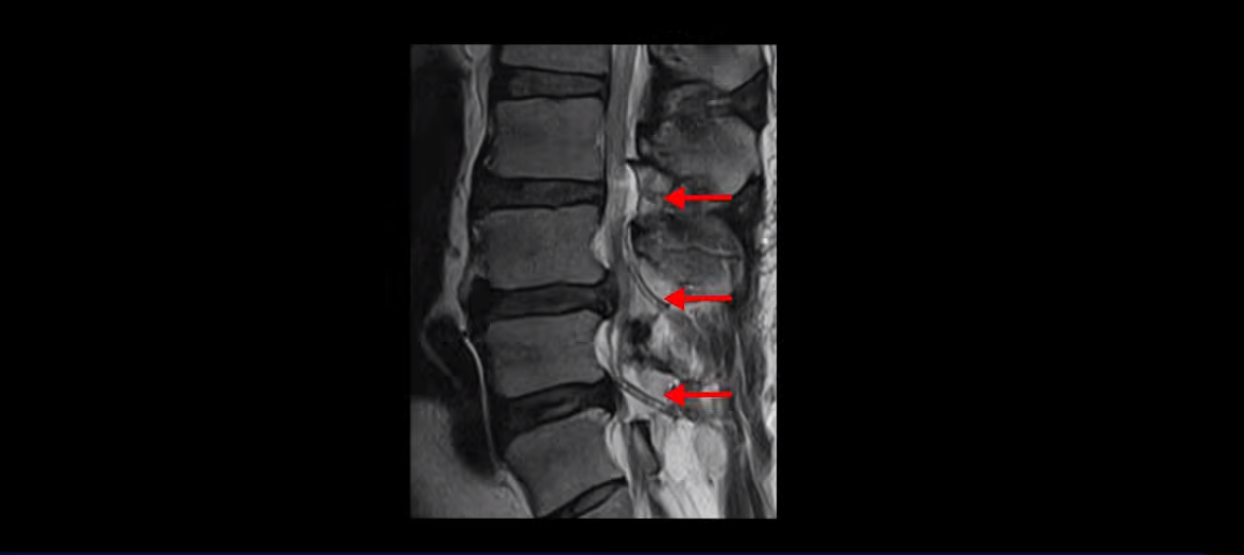

척수 신경이 눌리고 손상되니까 양쪽 손과 양쪽 다리 모두에 증상이 생깁니다. 양손에 힘이 빠지고 젓가락질이 힘들고, 단추 끼우기도 어려워지고 다리에 힘이 빠지니까 걷기도 힘들어집니다. 양손과 다리의 감각도 떨어지고요. 그래서 이 환자분은 수술하더라도 목 수술을 해야 하는데, 엉뚱하게도 허리 수술을 받습니다. 처음에 병원에 갈 때 허리도 원래 많이 아팠다고 하니까 그 병원에서 목 검사와 허리를 함께 검사해 보고 허리 협착도 심하니까 허리 수술을 먼저 하자고 합니다. 그래서 허리 세 마디를 수술했습니다.

MRI 보면 무려 3마디의 허리 뒤쪽, 후궁 뼈 한쪽을 거의 다 뜯어내고

황색 인대를 대부분 다 걷어냈습니다.

문제는 이 허리 협착이 양손과 양쪽 다리 힘 빠짐의 원인이 아니었기에 수술 후에도 증상이 전혀 좋아지질 않습니다. 그나마 다행인 건 허리 여러 마디를 수술하면서도 나사를 안 박은 겁니다. 수술로 인해 허리 여러 마디에 손상이 생기니까 걷기가 더 어려워져서 결국 저희 병원에 오실 때는 휠체어를 타고 오셨습니다.